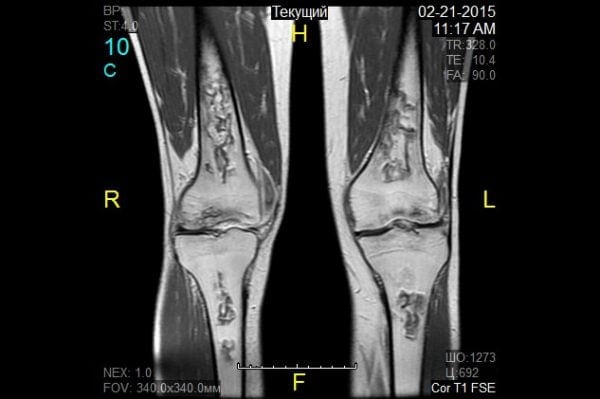

МРТ — современный и наиболее информативный диагностический метод. Он позволяет визуализировать повреждения костей и связочно-сухожильного аппарата. На полученных снимках МРТ коленного сустава хорошо видны все нарушения целостности составляющих его элементов.

Здоровые ткани выглядят на полученных изображениях в виде слабоокрашенных участков. Они четко дифференцированы в зависимости от своей плотности. Врач-диагност без затруднений выделяет нервное или мышечное волокно, соединительные структуры коленного сустава. Поврежденные элементы определяет по их окрашиванию, хорошо заметному на фоне здоровых тканей. Что показывает МРТ коленного сустава:

С помощью полученных изображений МРТ коленного сустава врач-диагност устанавливает вид возникшей патологии. Он учитывает изменение размеров суставной щели, образовавшиеся костные краевые дефекты и деструктивные кистозные очаги околосуставной костной ткани. Одним из определяющих признаков инфекционного артрита являются сформировавшиеся секвестры — омертвевшие участки ткани, отделяющиеся от здоровых. При помощи магнитно-резонансной томографии устанавливаются характерные для суставных патологий локальные изменения теплообмена. Во многих случаях возможно обнаружение экссудата в колене.